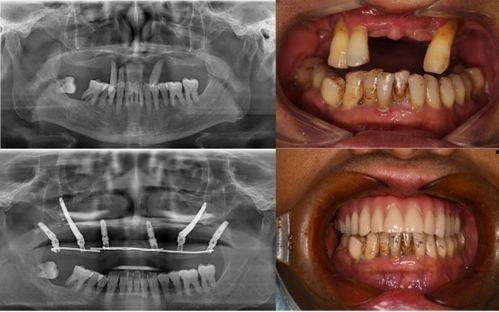

最近佛山那边的种牙事件可是闹得沸沸扬扬的,咱们得好好来聊聊这个话题。你有没有听说,佛山某口腔医院因为种牙问题引发了一场不小的风波?别急,让我带你一探究竟,看看这背后到底隐藏着怎样的秘密。一、事件起因:患者反映种牙后问题不断话...